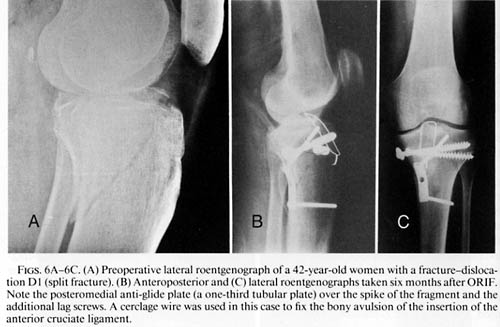

The objective of treatment of tibial plateau fractures is precise reconstruction

of the articular surfaces, stable fragment fixation allowing early motion, and

repair of all concomitant lesions. A classification scheme is employed to

include the high incidence of concomitant lesions in specific fracture types.

classification system of closed and open soft-tissue injury. Preferred treatment

is open reduction and internal fixation (ORIF) in all displaced and unstable

tibial plateau fractures. A stepwise approach is used in complex knee trauma.